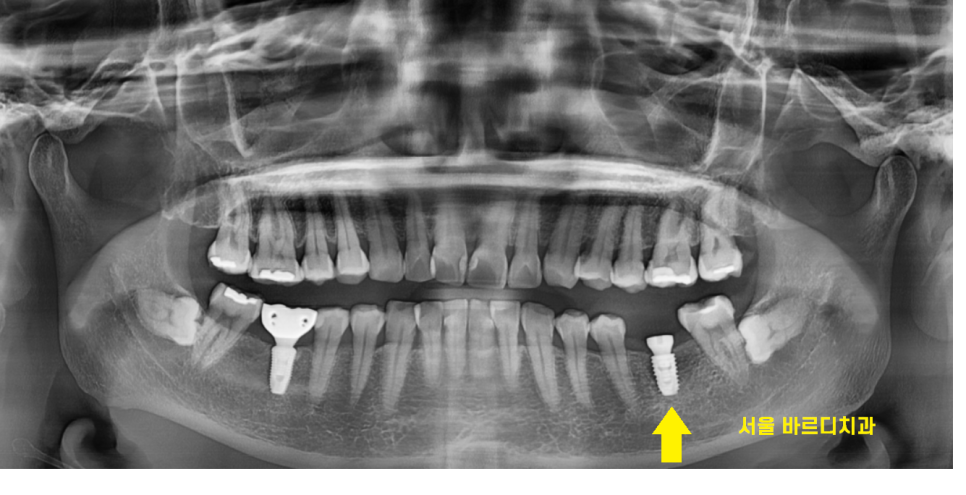

23.12.19

환자분께서 풍산동 치과 처음 방문해주셨을 때

이 뺀 자국이 그대로 남아 있는 상태에서

방문해주셨습니다.

다른 곳에서 저 부분에 뼈이식을 해야한다고 들어서

풍산동 치과를 방문해주셨다 하셨습니다.

이를 뺀 지 얼마 안됐을경우

뼈가 아직 덜 차서 저렇게 흔적이 남을 수 있는데요.

정확한것은 더 검사를 해봐야겠지만

1차적으로만 파노라마 사진을 보았을 때

뼈 이식

제가 보기에는 필요 없어보였습니다.